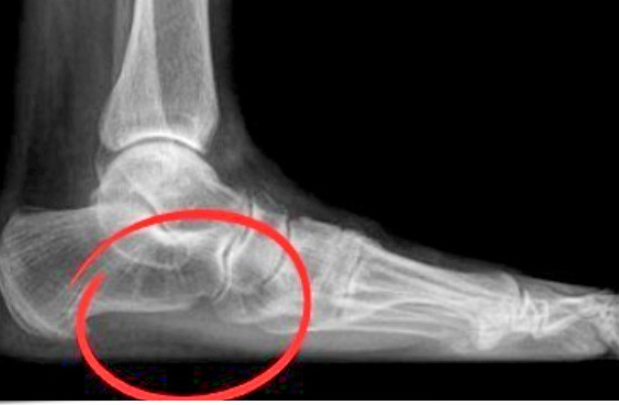

염증이 오래 지속되면 족저근막이 점차 두꺼워지고, 발뒤꿈치 뼈에 석회성 돌기(Heel Spur)가 형성되기도 합니다. 통증이 지속적이며, 휴식 중에도 찌릿하거나 화끈거리는 느낌이 나타납니다. 이 단계에서는 단순 물리치료만으로는 회복이 어려워 전문적인 비수술 치료가 필요합니다.

족저근막염 진단은 대부분 문진과 촉진검사로 충분히 가능합니다. 의사는 통증의 위치, 발생 시기, 운동 습관 등을 분석하며 필요시 초음파나 MRI를 통해 염증의 범위를 확인합니다.